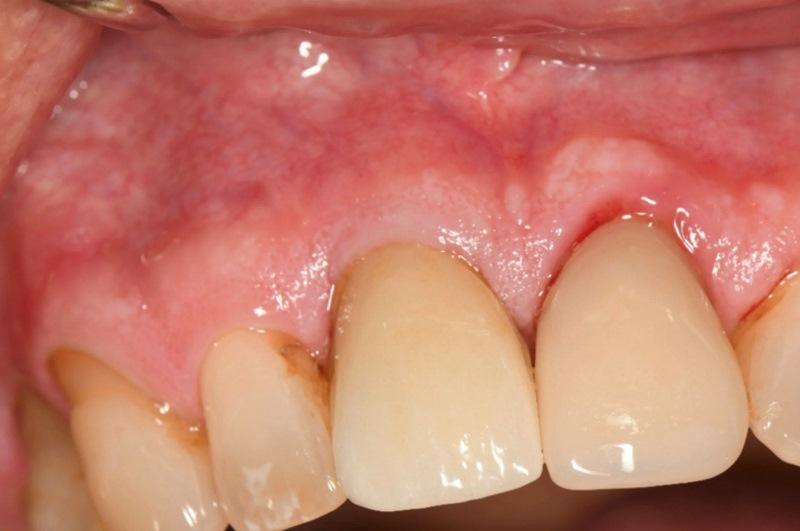

Через 4 месяца после установки имплантата пациент явился для контроля заживления и оценки остеоинтеграции. После снятия ретейнера Essix мягкие ткани вокруг индивидуального формирователя десны без признаков воспаления (Фото 8). Снятие формирователя десны выявило хорошо сформированный десневой манжет без воспалительных явлений (Фото 9). Показатель ISQ 72 подтвердил успешную остеоинтеграцию и готовность к протезированию.

Фото 8. Индивидуальный формирователь десны после завершения этапа интеграции имплантата.

Фото 9. После снятия формирователя отмечена сформированная десневая манжета без признаков воспаления.